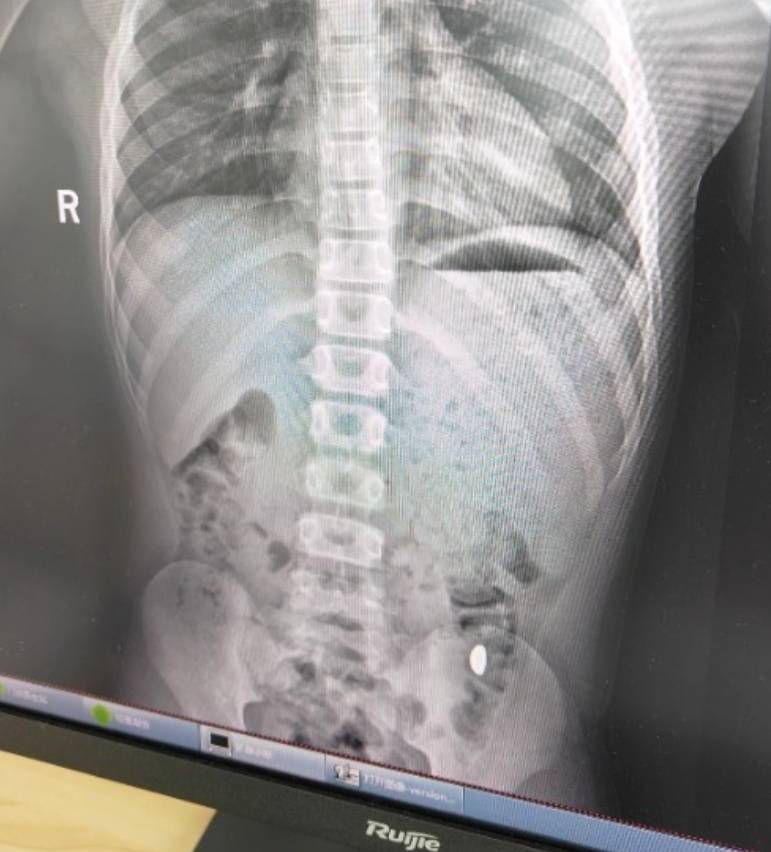

右下加亮点为金豆中原油田房产。